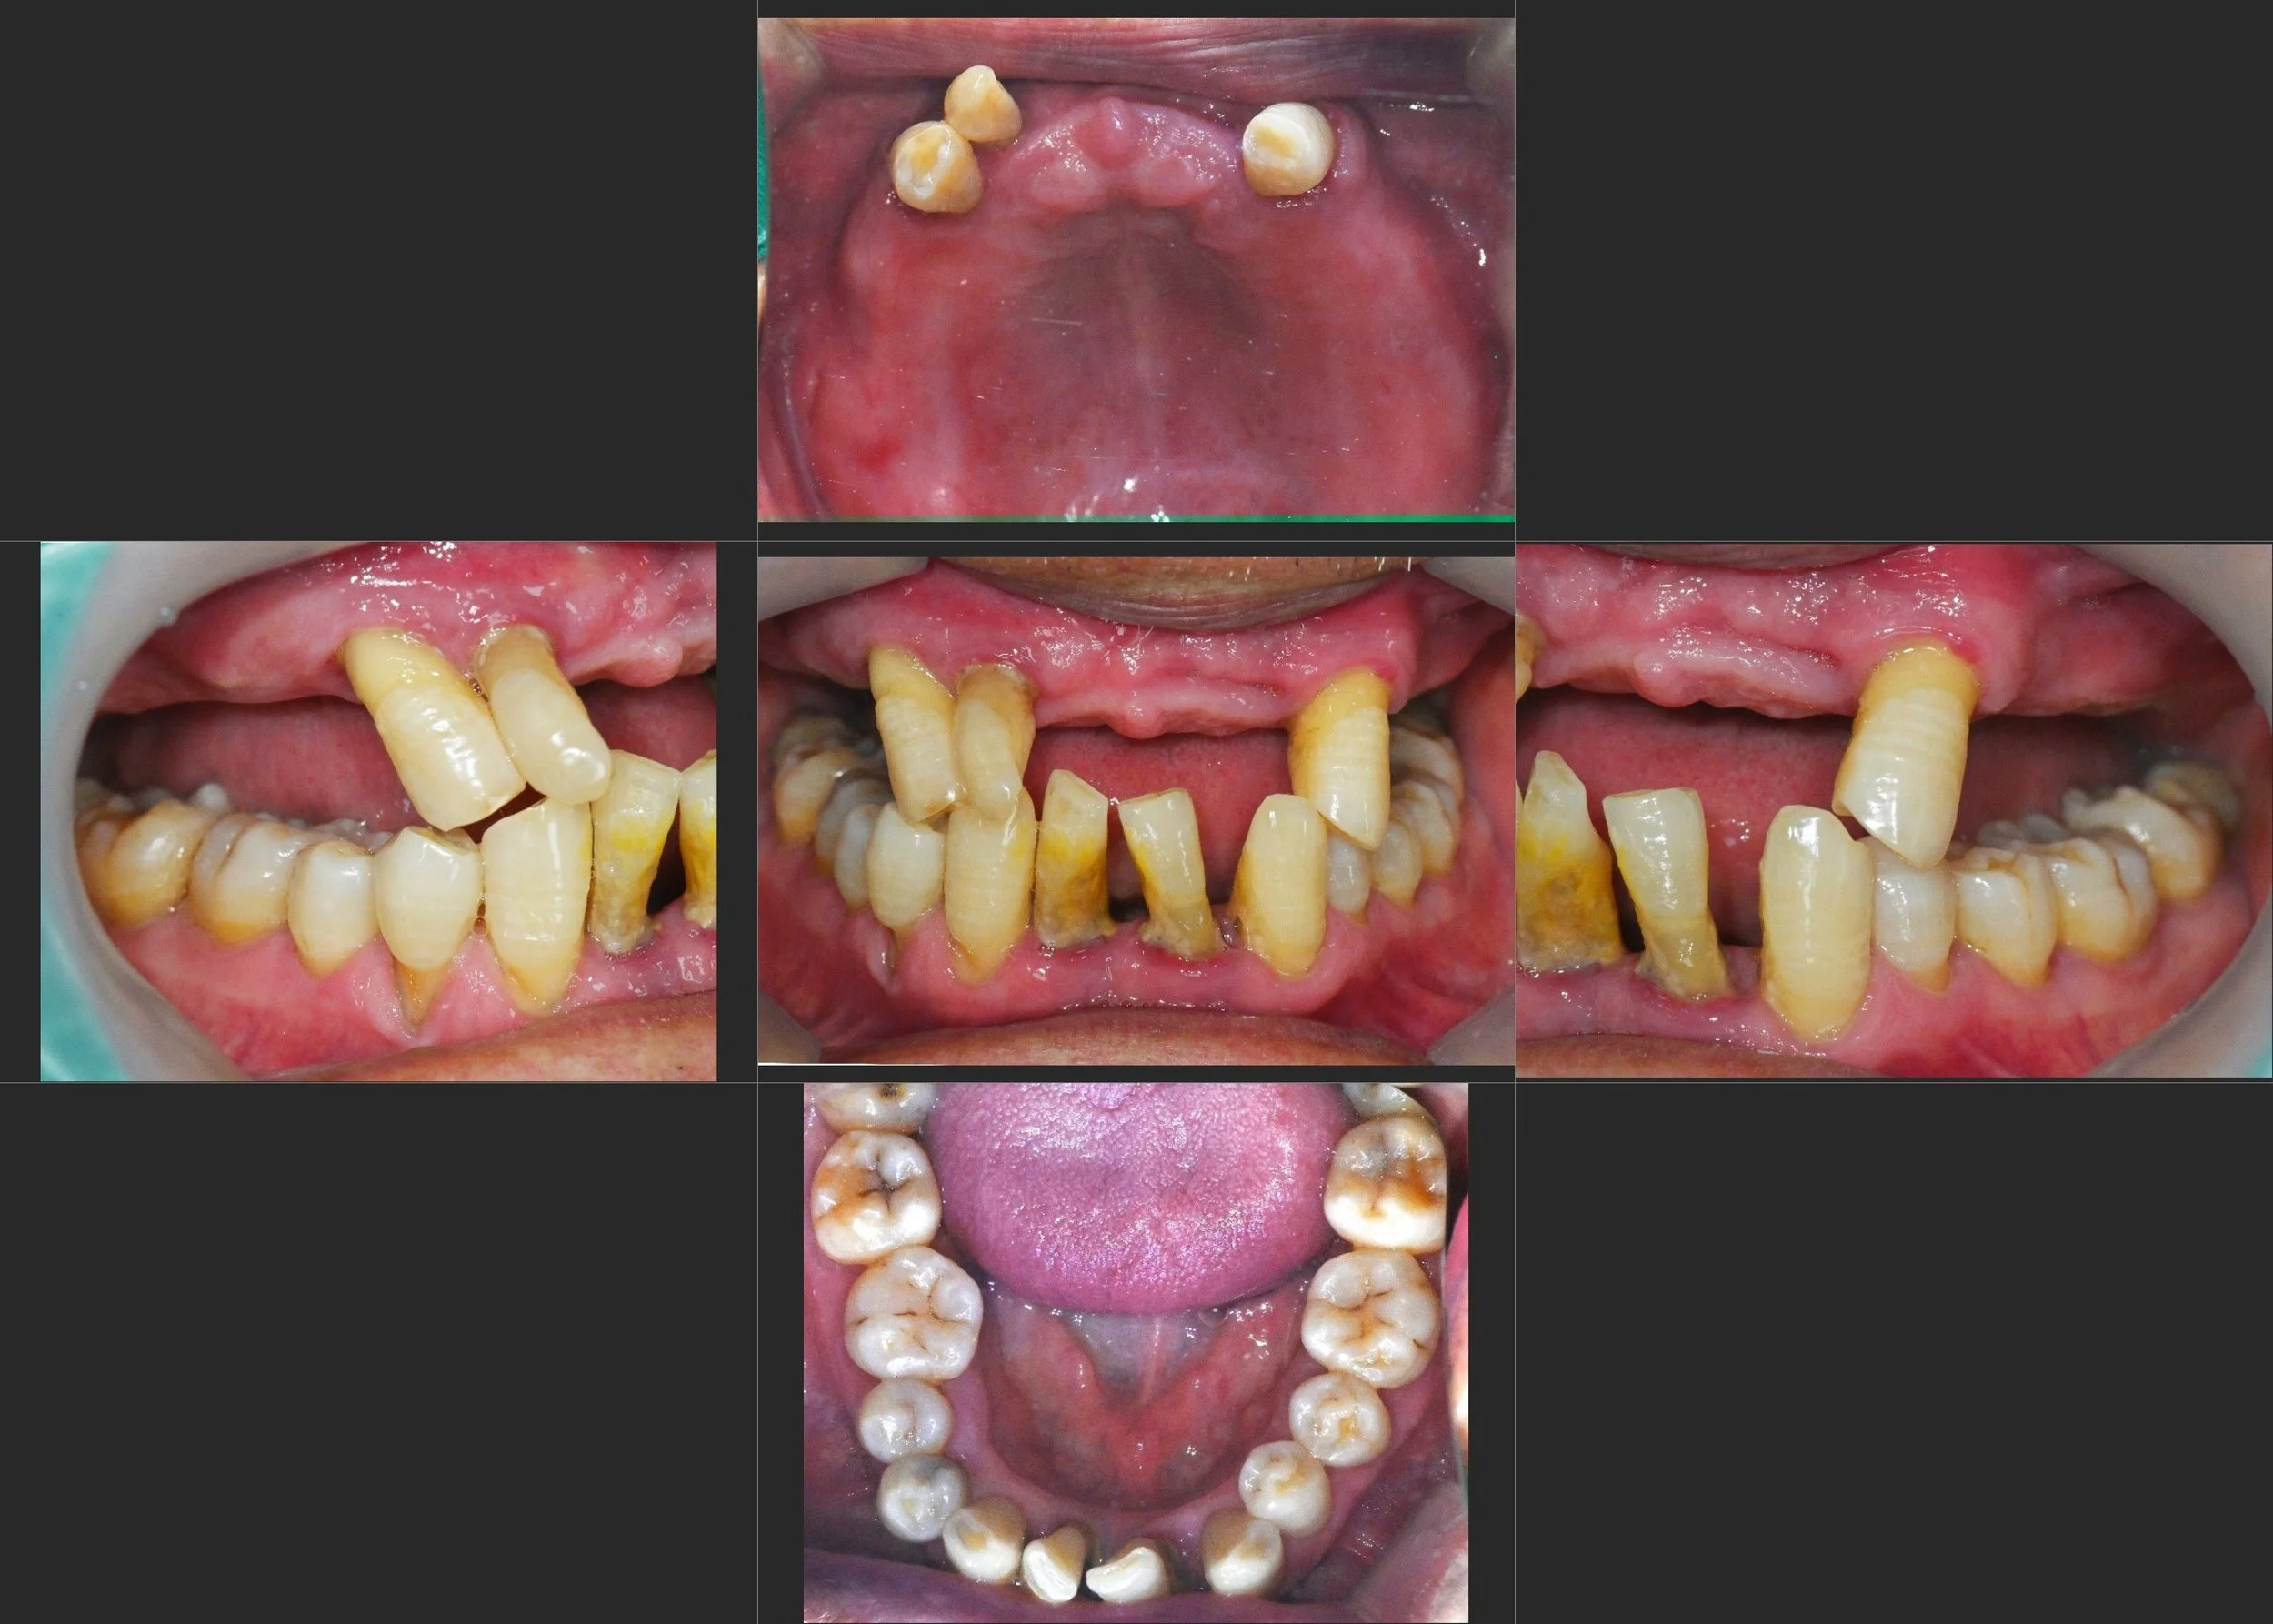

37. Reclaiming Functional Comfort: Correcting Iatrogenic Occlusal Failure

Resolution of Incomplete Mouth Closure and TMJ Instability in a Female Patient in her 60s. A Conservative but Definitive Approach through Selective Occlusal Adjustment and Posterior Implant Support.